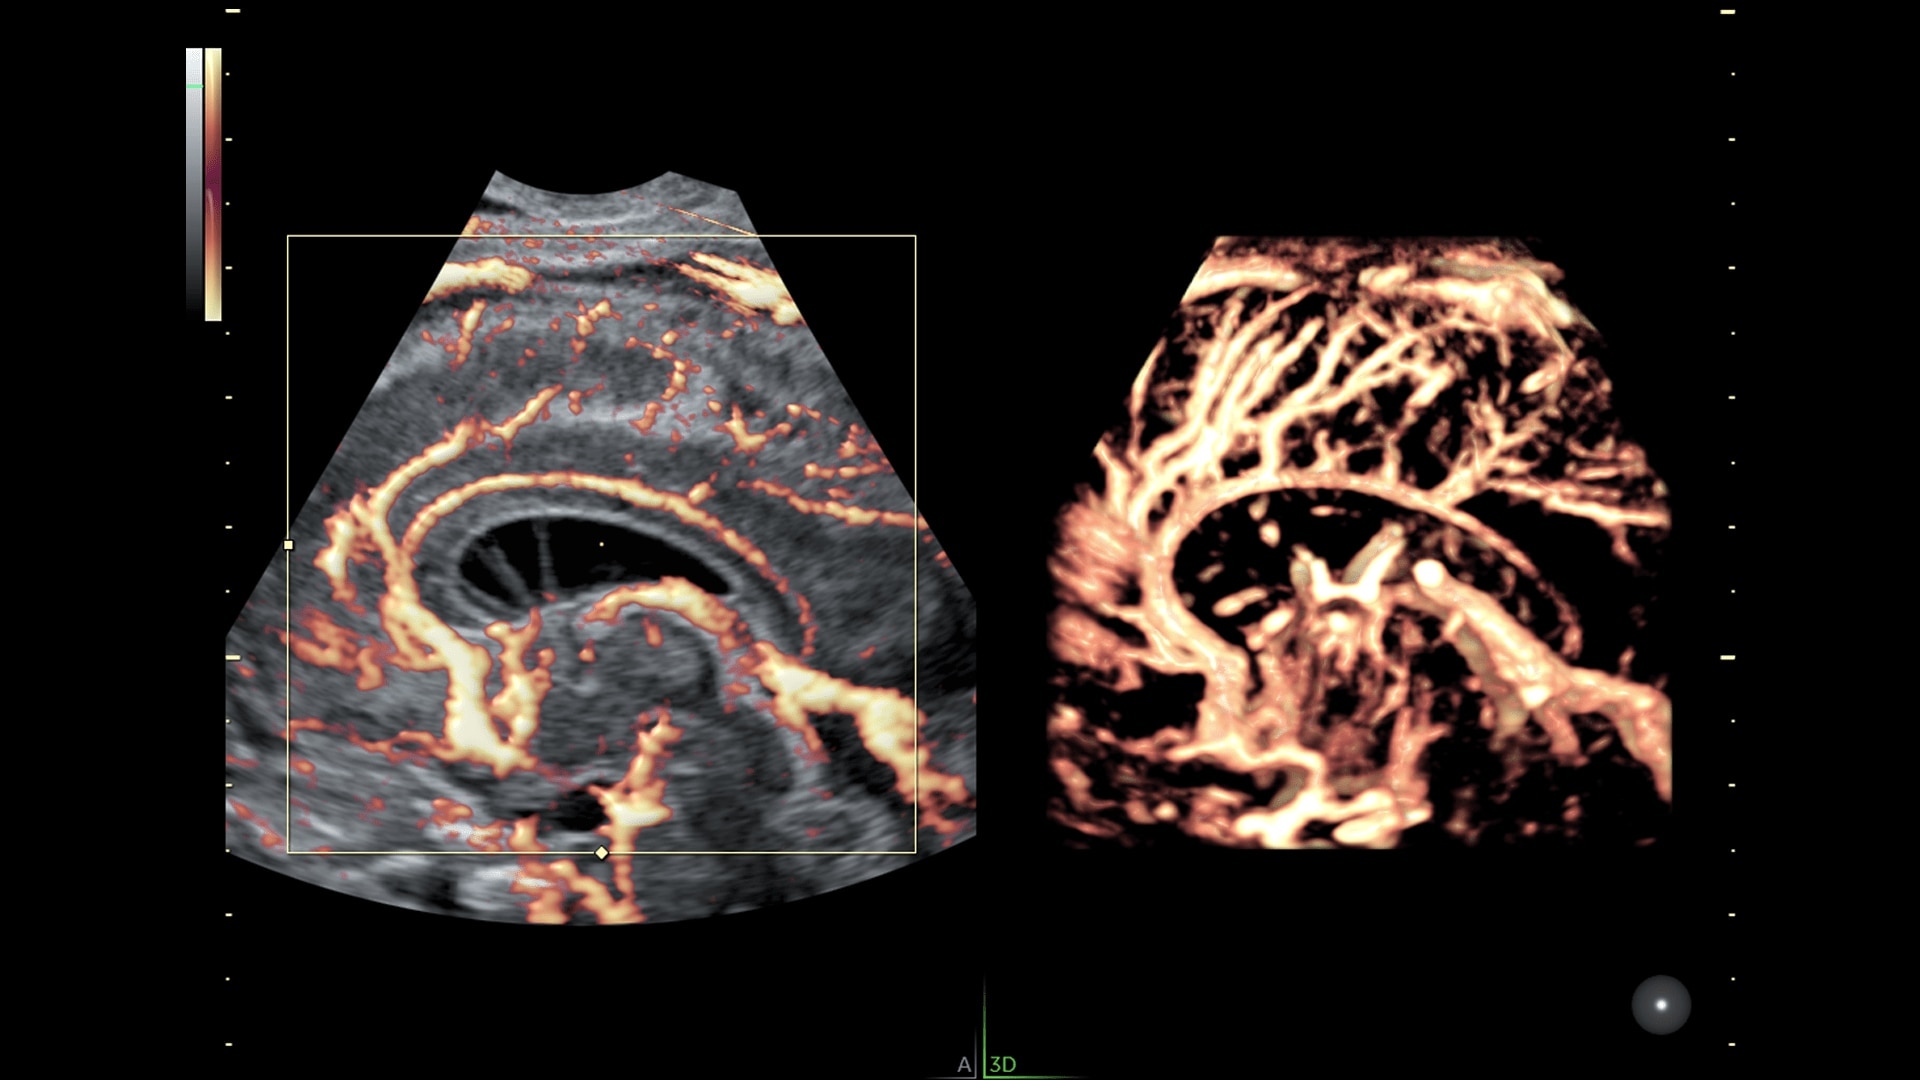

Enhanced Volume Imaging

Deliver next generation 3D/4D & Color images with HDlive Studio+